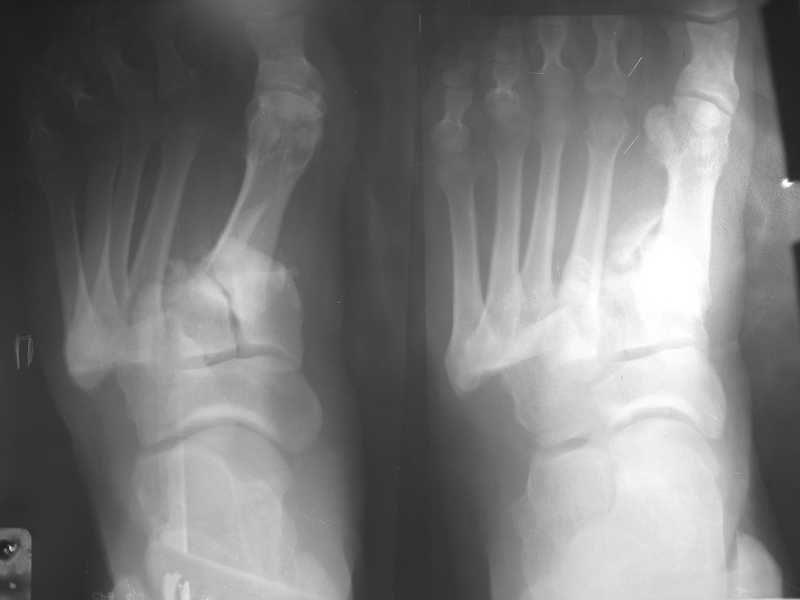

Обратился пациент, мужчина 42лет. для дальнейшего лечения. Травма 11.09., ДТП. 15.09 проведено оперативное лечение фиксаторами.)

(Блокирующий стержень левого бедра - статическая система. Открытое вправление вывиха в суставе Лисфранка и фиксация мет. фиксаторами.) D.S. Переломы диафиза и межмыщелковой области левого бедра, вывих в суставе Лисфранка правой стопы. Состояние после МОС. Через 6 нед. контрольная Ro,( снимки прилагаются).

По тактике дальнейшего лечения мнения разошлись.

По бедру :

1- учитывая межмыщелковый перелом статическая система 3 мес., и перевод в динамическую, наблюдение.

2- При такой Ro - картине будет ложный сустав или рефрактура после удаления стержня, и поэтому идти на пластину с костной пластикой.

По суставу Лисфранка :

1- 8 -9 нед . полный покой в гипсовой шине,а потом дозированная нагрузка.

2- Сейчас (на 7 нед.) пригипсовать каблук под пятку и давать дозированную нагрузку, и на 12 нед, одновременно с переводом статической системы в динамическую провести удаление фиксаторов из стопы.

Какую тактику посоветуете Вы ?.